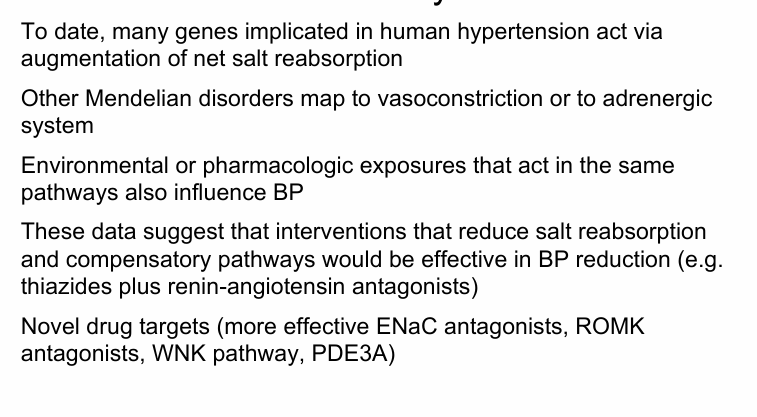

distribution of bp in US and Canada- age related increase in bp